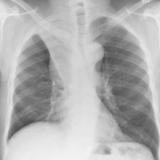

Gallery Lobar Collapse

Lobar Collapse

LUL Collapse

Album: LUL Collapse

LLL Collapse

Album: LLL Collapse

RLL Collapse

Album: RLL Collapse

RUL Collapse

Album: RUL Collapse

RML Collapse

Album: RML Collapse